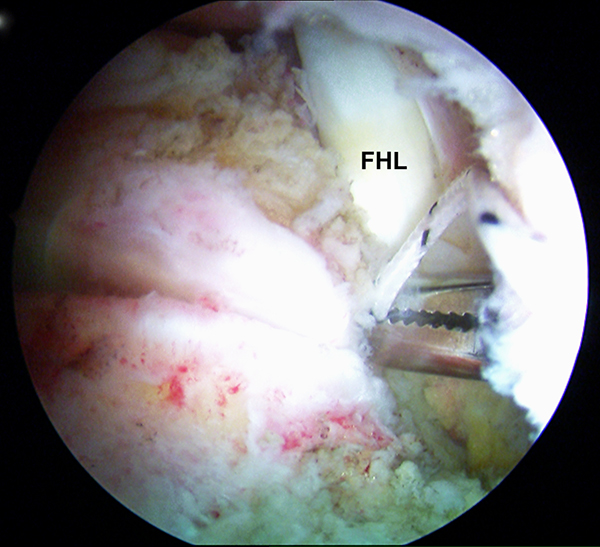

Abbildungen 9-11, Video 3

In maximaler Plantarflexion des Fußes wird die FHL-Sehne durch kräftigen Zug an den Fadenenden nach kranial mobilisiert und soweit wie möglich distal tenotomiert. Die Tenotomie kann mit einer feinen Schere, einem Punch oder mit einem 11er Skalpell über den posteromedialen Arthroskopiezugang durchgeführt werden. Für die Tenotomie sollte eine gute Übersicht vorhanden sein, um eine Verletzung des Gefäß-Nerven-Bündels zu vermeiden. Der Sehnenstumpf wird aus dem posteromedialen Portal ausgeleitet.